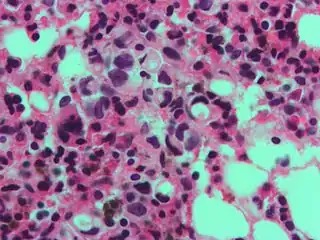

Gastric signet ring cell carcinoma. H&E stain.

The name of the cell comes from its appearance; signet ring cells resemble signet rings. They contain a large amount of mucin, which pushes the nucleus to the cell periphery. The pool of mucin in a signet ring cell mimics the appearance of a finger hole and the nucleus mimics the appearance of the face of the ring in profile.

Appearance